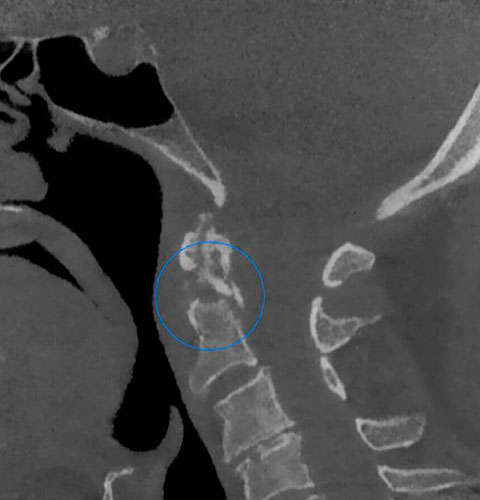

Veja exemplos de diagnósticos de imagem

- O gerador com ânodo giratório e ponto focal de 0,3 mm permite obter imagens de altíssima definição para ver detalhes e microestruturas que não podem ser investigados com dispositivos tecnológicos padrão;

- Algoritmos de reconstrução e processamento de imagem, resultado dos vinte anos de experiência da NewTom, permitem obter rapidamente imagens 2D e 3D excepcionais.